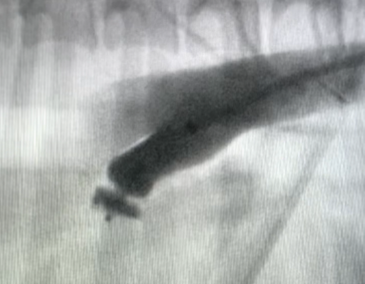

Step three: A delivery sheath is positioned across the PDA into the pulmonary artery, and the ACDO device is inserted through the sheath. The distal disc of the ACDO is exposed before the sheath and ACDO device are then retracted together until the distal disc meets the pulmonary opening of the PDA (Figure 5). The ACDO device is held in place while the delivery sheath is retracted, deploying the waist of the device into the MDD of the PDA and the proximal disc within the ductal ampulla (Figure 6). Gentle to-and-fro manipulation of the device delivery cable is applied to ensure correct positioning.

Step four: A waiting period of 5 to 10 minutes is typically allowed for haemostasis in the ductus. Then the device is released from the end of the delivery cable by clockwise rotation of the wire. A post-release angiogram can be performed, which typically indicates complete occlusion of the PDA (Figure 7). A small volume of residual flow is not considered abnormal and is likely to fully occlude in the coming hours or days.